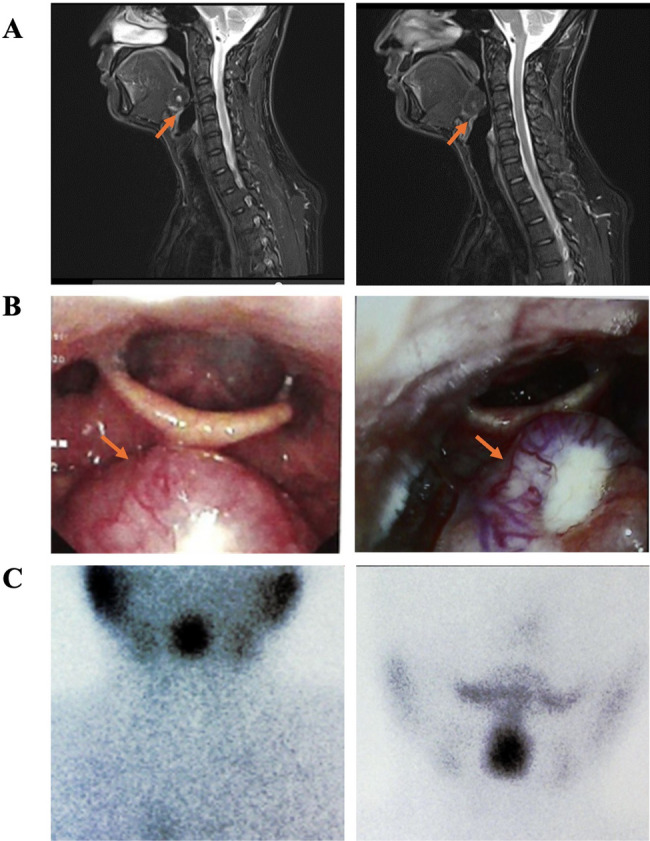

Case presentation: A 37-year-old male military helicopter pilot was incidentally diagnosed with lingual thyroid during routine health screening. The patient remained asymptomatic throughout the clinical course. Comprehensive evaluations-including thyroid function tests, biochemical profiling, cervical magnetic resonance imaging, electronic laryngoscopy, radionuclide scanning, and portable sleep monitoring-confirmed the presence of a lingual thyroid with subclinical hypothyroidism. Imaging demonstrated the ectopic tissue at the tongue base to be the sole functioning thyroid gland. Levothyroxine therapy was initiated, resulting in normalization of thyroid hormone levels. Polysomnography was performed due to the anatomical location of the lesion and excluded obstructive sleep apnea or ventilatory compromise. Given the patient's strong motivation to resume flight duties, a multidisciplinary aeromedical evaluation was conducted. Based on clinical stability, absence of symptoms, and treatment response, the pilot was deemed aeromedically fit. Since June 2021, he has accumulated over 900 flight hours, with preserved thyroid function and no evidence of disease progression on longitudinal follow-up.